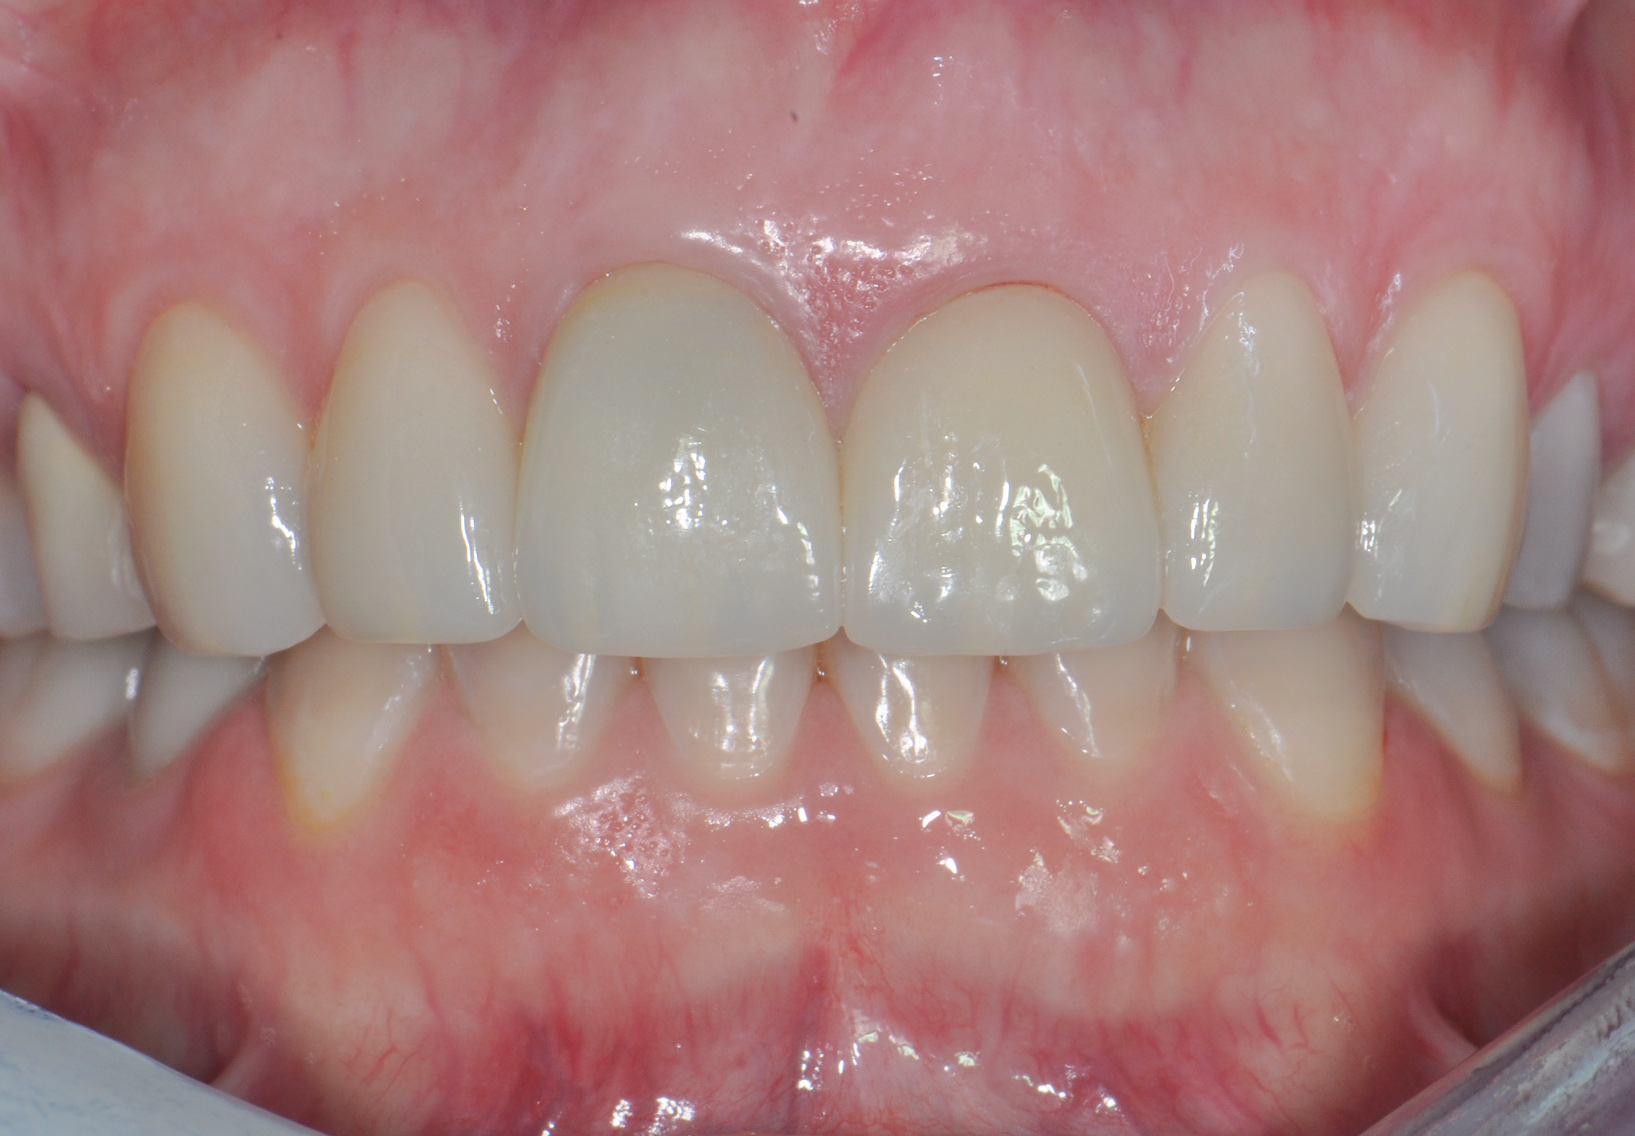

Fig 10. Completed crowns at 5 years, angled view. Note the convex contours facial to implant No. 9 attributed to the connective tissue grafting.

Figure 10

Figure 8 shows the provisionalization of No. 8 at 6 weeks postoperatively and a screw-retained provisional restoration on No. 9 to develop the subgingival transitional zone (key Nos. 8 through 10). The transitional zone will be duplicated using the custom impression coping technique. Figure 9 and Figure 10 depict the completed crowns at 5 years; implant No. 9 was screw-retained (key No. 10). In Figure 10 note the convex contours facial to implant No. 9 that are attributed to the connective tissue grafting as part of the surgical protocol creating biotype conversion from a thick to a thicker biotype. Figure 11 through Figure 13 show 5-year postoperative patient smile, periapical x-ray, and CBCT, respectively.